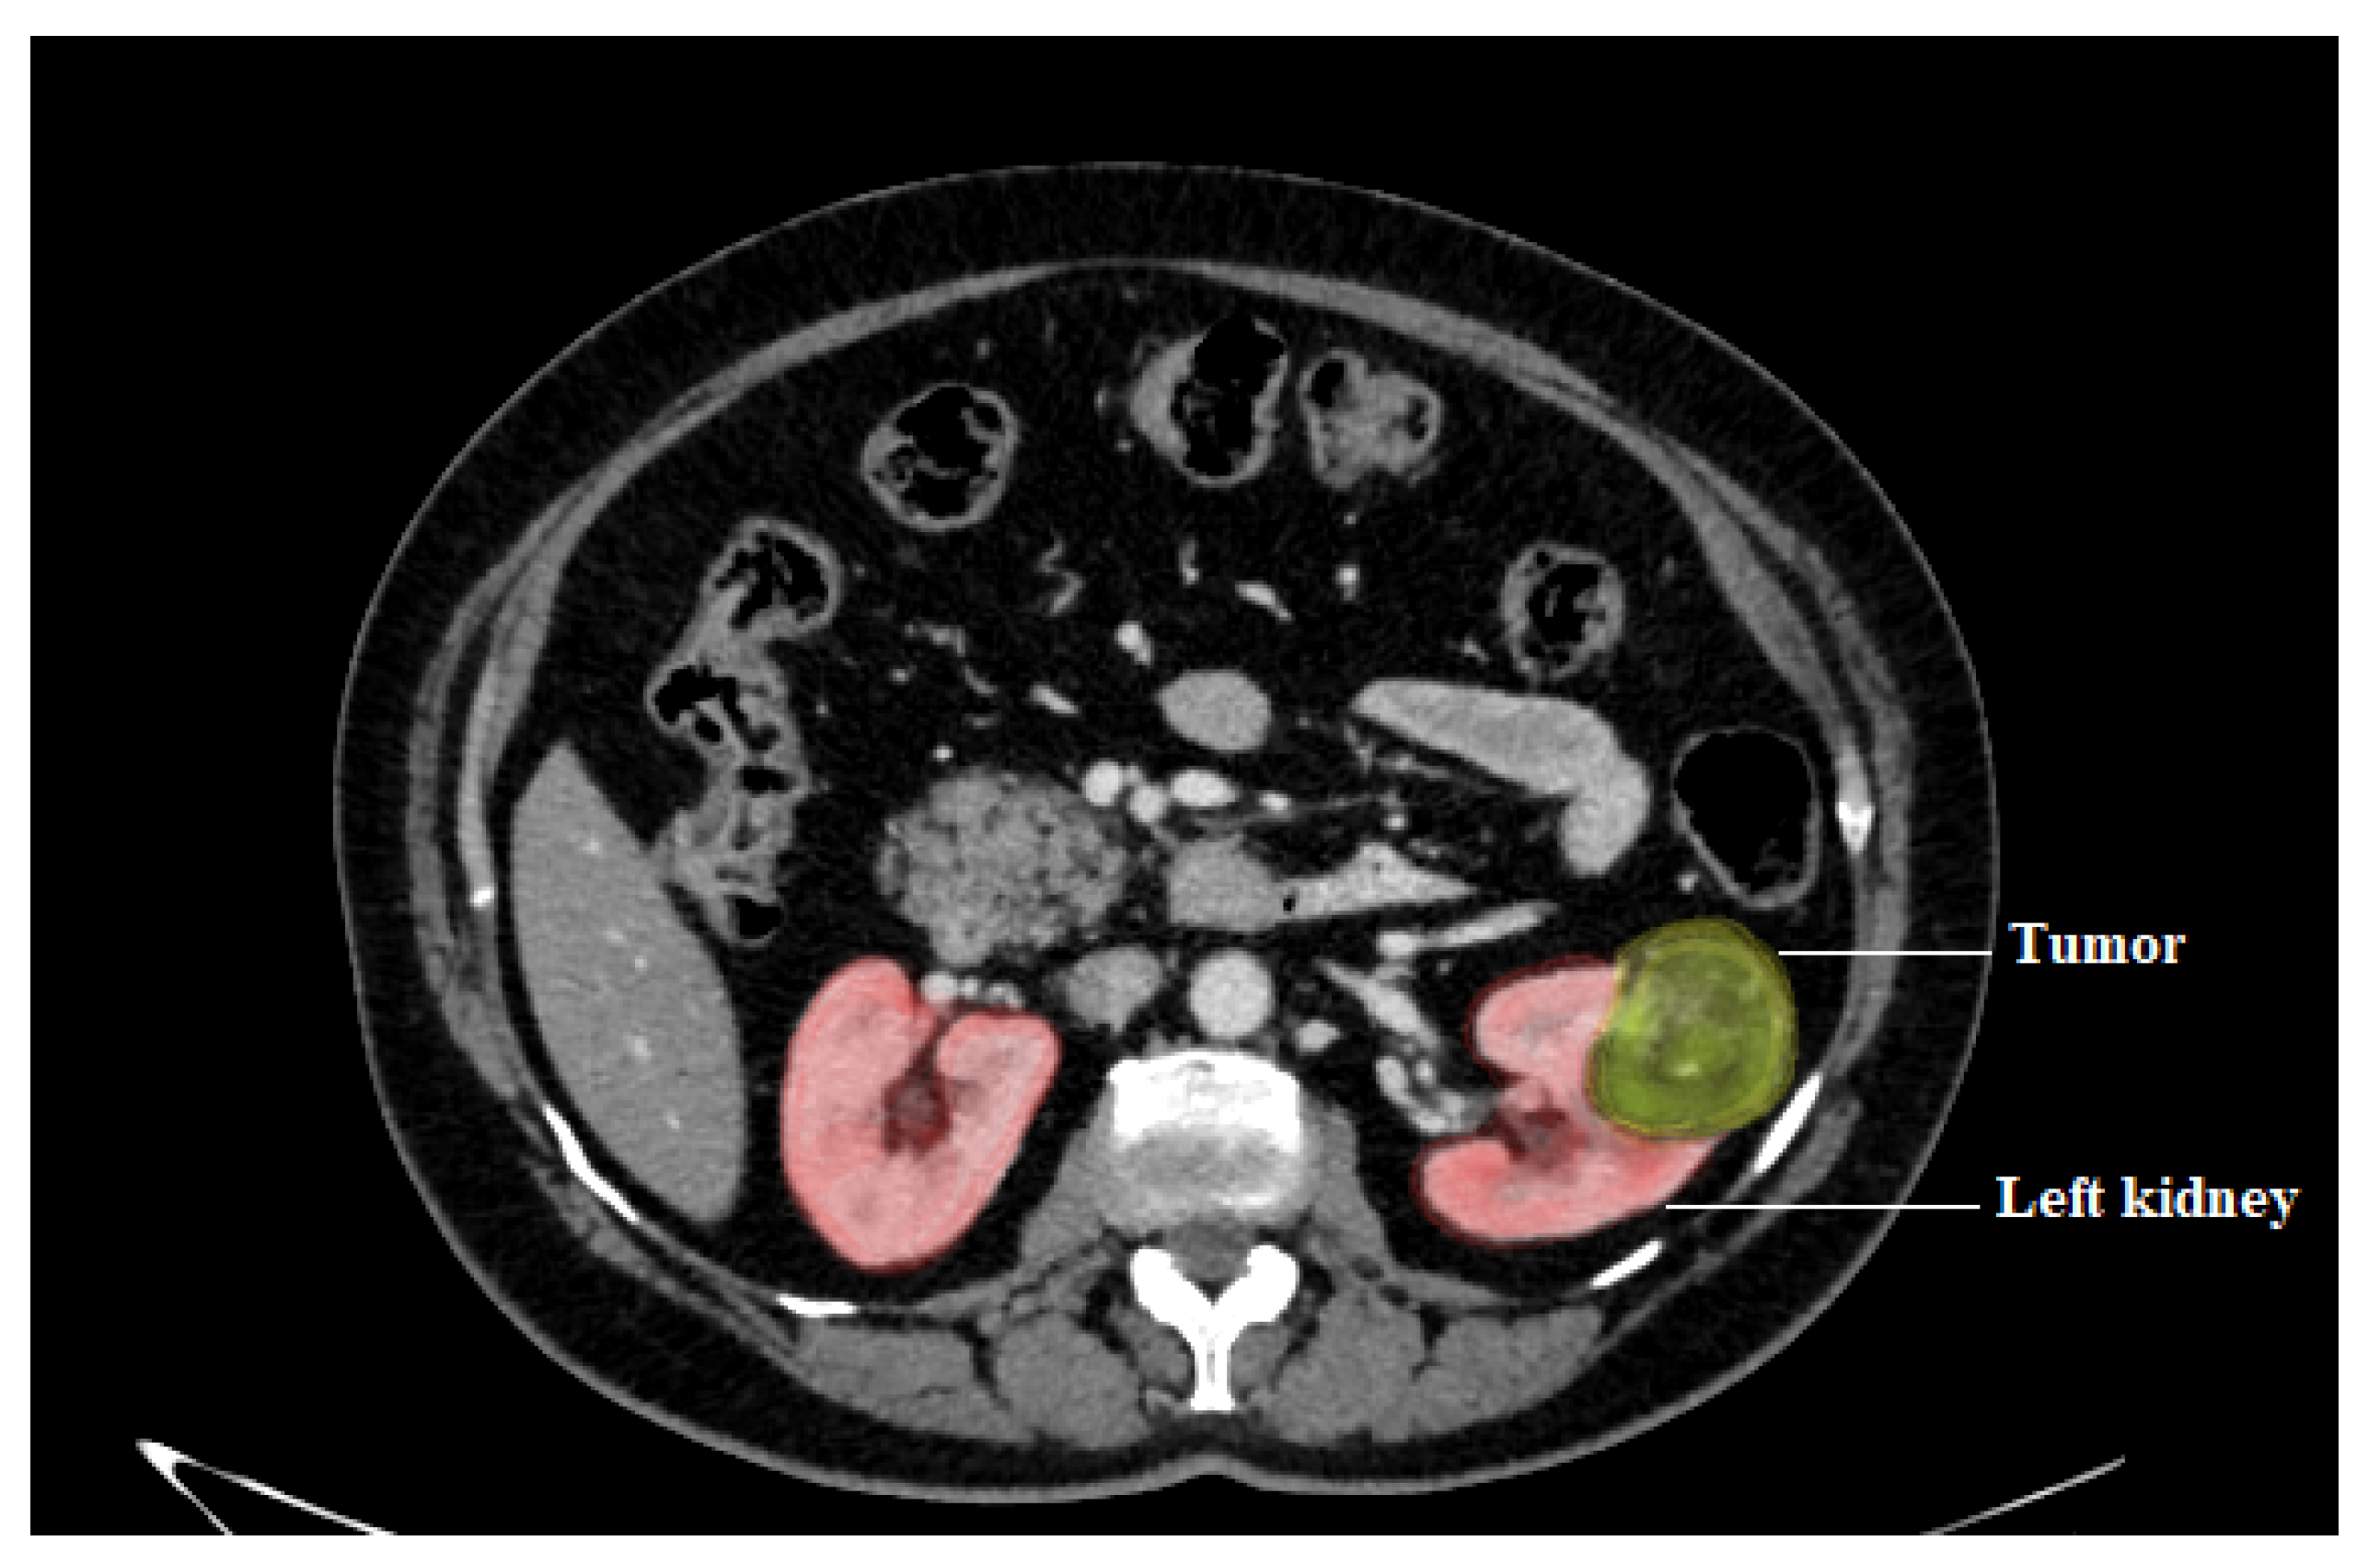

Image segmentation is usually used to detect objects and boundaries (curves, lines, edge, color, intensity, or texture) in images [84,85,86]. The purpose is to re-represent an image in a more meaningful and easier-to-interpret manner. Image segmentation, to put it another way, is the method of allocating a label to each pixel in an image such that pixels with the same label have similar characteristics. Segmentation can be more complex than classification, which contains multiple texture regions in the same picture. The aim is to find areas with uniform texture and correctly mark them with their appropriate classes, taking into account texture borders where windows samples can include multiple textures [87]. Accurate segmentation of Kidney Tumors is critical for subsequent prognosis and treatment planning. Figure 16 shows a segmentation for kidney tumor and renal mass lesion in the left kidney, measuring about 4 cm. Table 5 indicates the outcomes of the related segmentation tumor studies based on CT scans, which were categorized using the following criteria.

Figure 16.

Kidney tumor segmentation.